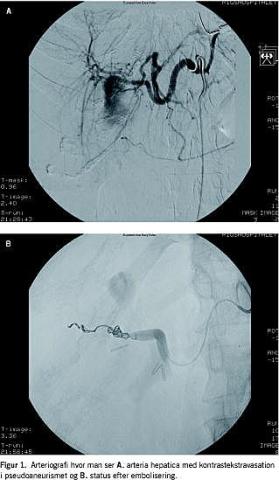

En 35-årig kvinde, der tidligere var blevet behandlet med endoskopisk retrograd kolangiopankreatikografi (ERCP) og papillotomi pga. choledochussten blev elektivt laparoskopisk kolecystektomeret. Operationen forløb ukompliceret, med fjernelse af en lille, skrumpet galdeblære med enkelte konkrementer. Patienten blev udskrevet i velbefindende samme dag, men genindlagt 13 dage efter med abdominalsmerter. Ved en ultralydskanning (UL) blev der fundet fri væske nedadtil i abdomen, og en prøvepunktur viste blod. Da patienten var cirkulatorisk upåvirket, blev hun behandlet konservativt og udskrevet to dage senere. Hun blev genindlagt tre dage senere, igen pga. smerter og fald i hæmoglobinniveau. UL med Doppler viste et 3-5 cm aneurisme i hilusområdet. Fundet blev bekræftet ved en computertomografi, hvorefter patienten blev overflyttet til et større, specialiseret center til radiologisk embolisering (coiling ) af pseudoaneurismet (Figur 1 A og B). Emboliseringen blev udført akut, da patienten var hæmodynamisk påvirket med hæmoglobinfald, hvilket tydede på akut blødning fra pseudoaneurismet. Emboliseringen blev udført med succes. Patienten var efterfølgende indlagt i en længere periode af andre årsager, der ikke var relaterede til selve aneurismet (choledochussten med kolangitis).